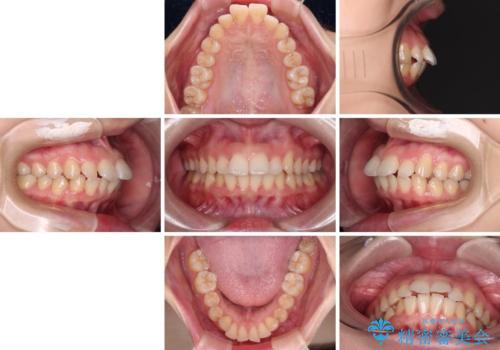

口が閉じられない ワイヤー装置での抜歯矯正

- 上下の前歯が突出しており、口が閉じにくいとのことで来院された患者様です。

上下前歯が著しく前突している状態であったので、上下左右の第1小臼歯4本を抜歯し、ワイヤー装置にて矯正治療を行うこととしました。

舌の突出癖により、前突になったと考えられたため、舌のトレーニングをしっかりと行うよう指導しました。